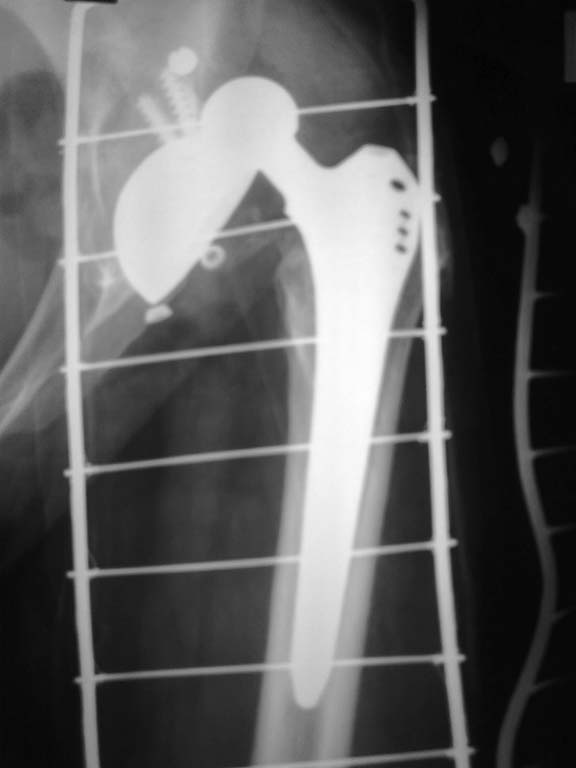

после вправления.

Все получилось из переднего доступа по Лайт-Кегги под эопом конечно смотрели казалось нестабильна,но на самом деле чашка не качалась,остеоинтеграция была только в зоне винтов , остальное рубцова ткань -гладкая и блестящая.После сбивания головки бедро в положении внутренней ротаци сместили вверх и впадина очень хорошо доступна. Установили чашку DePuy Pinnacle с антеверсией 20 гр. Востановить офсет удалось с головкой DePuy +12. Рентген контроль на С-дуге интраоперационно.

Да конечно чашка была нестабильна.Больная завтра идет домой,вот обзорная таза.

Ну вот, другое дело. Сравните снимке до и после, увидете разницу, насколько разнятся стояния чашек и по глубине и по углу инклинации.Молодцы. Я Вас Поздравляю.